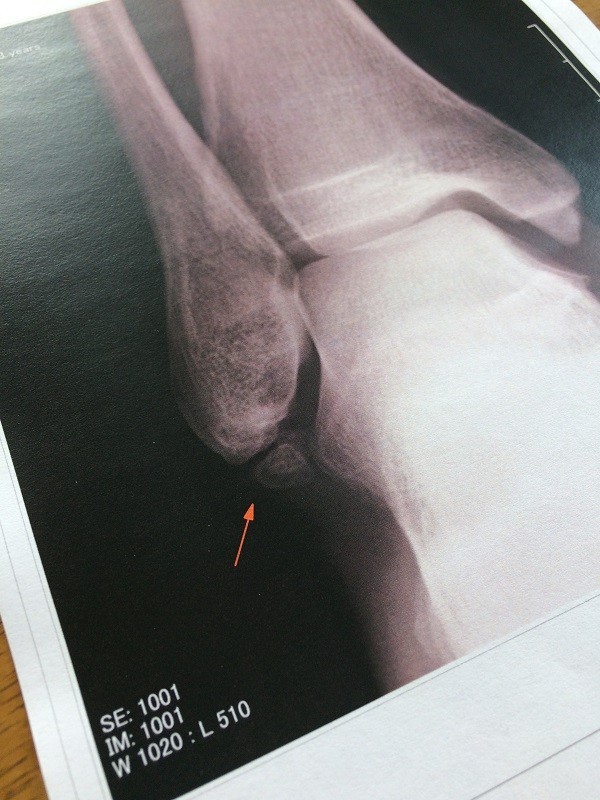

一方、右足首の痛みが完全には引かないので整形外科に行ったら「骨折した跡があります。付き合って行くしかないね」的なコメントで…

でもやっぱり「付き合って行くしかないね」では納得できないので紹介状を書いてもらってスポーツ整形外科へ。夕霧TT 2017-Stage2でコロちゃんが漢の走りを見せた今日、MRIを撮ってきた。

先日のCTの結果と合わせ、全容が間もなく判明する。良い流れに変えていきたい。